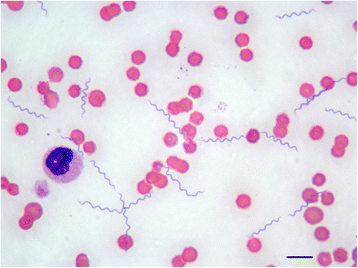

Лептоспиры: фотографии удивительных микроорганизмов